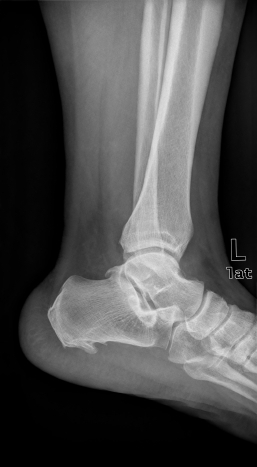

Артрография

Описание услуги - Артрография

Артрография осуществляется наметить суставы и связки. Краситель вводится в сустав и рентгеновские лучи приняты с целью выявления любых травм.

Типичные осложения:Повреждение суставов, инфекции, кровотечения, или аллергическая реакция на краску.